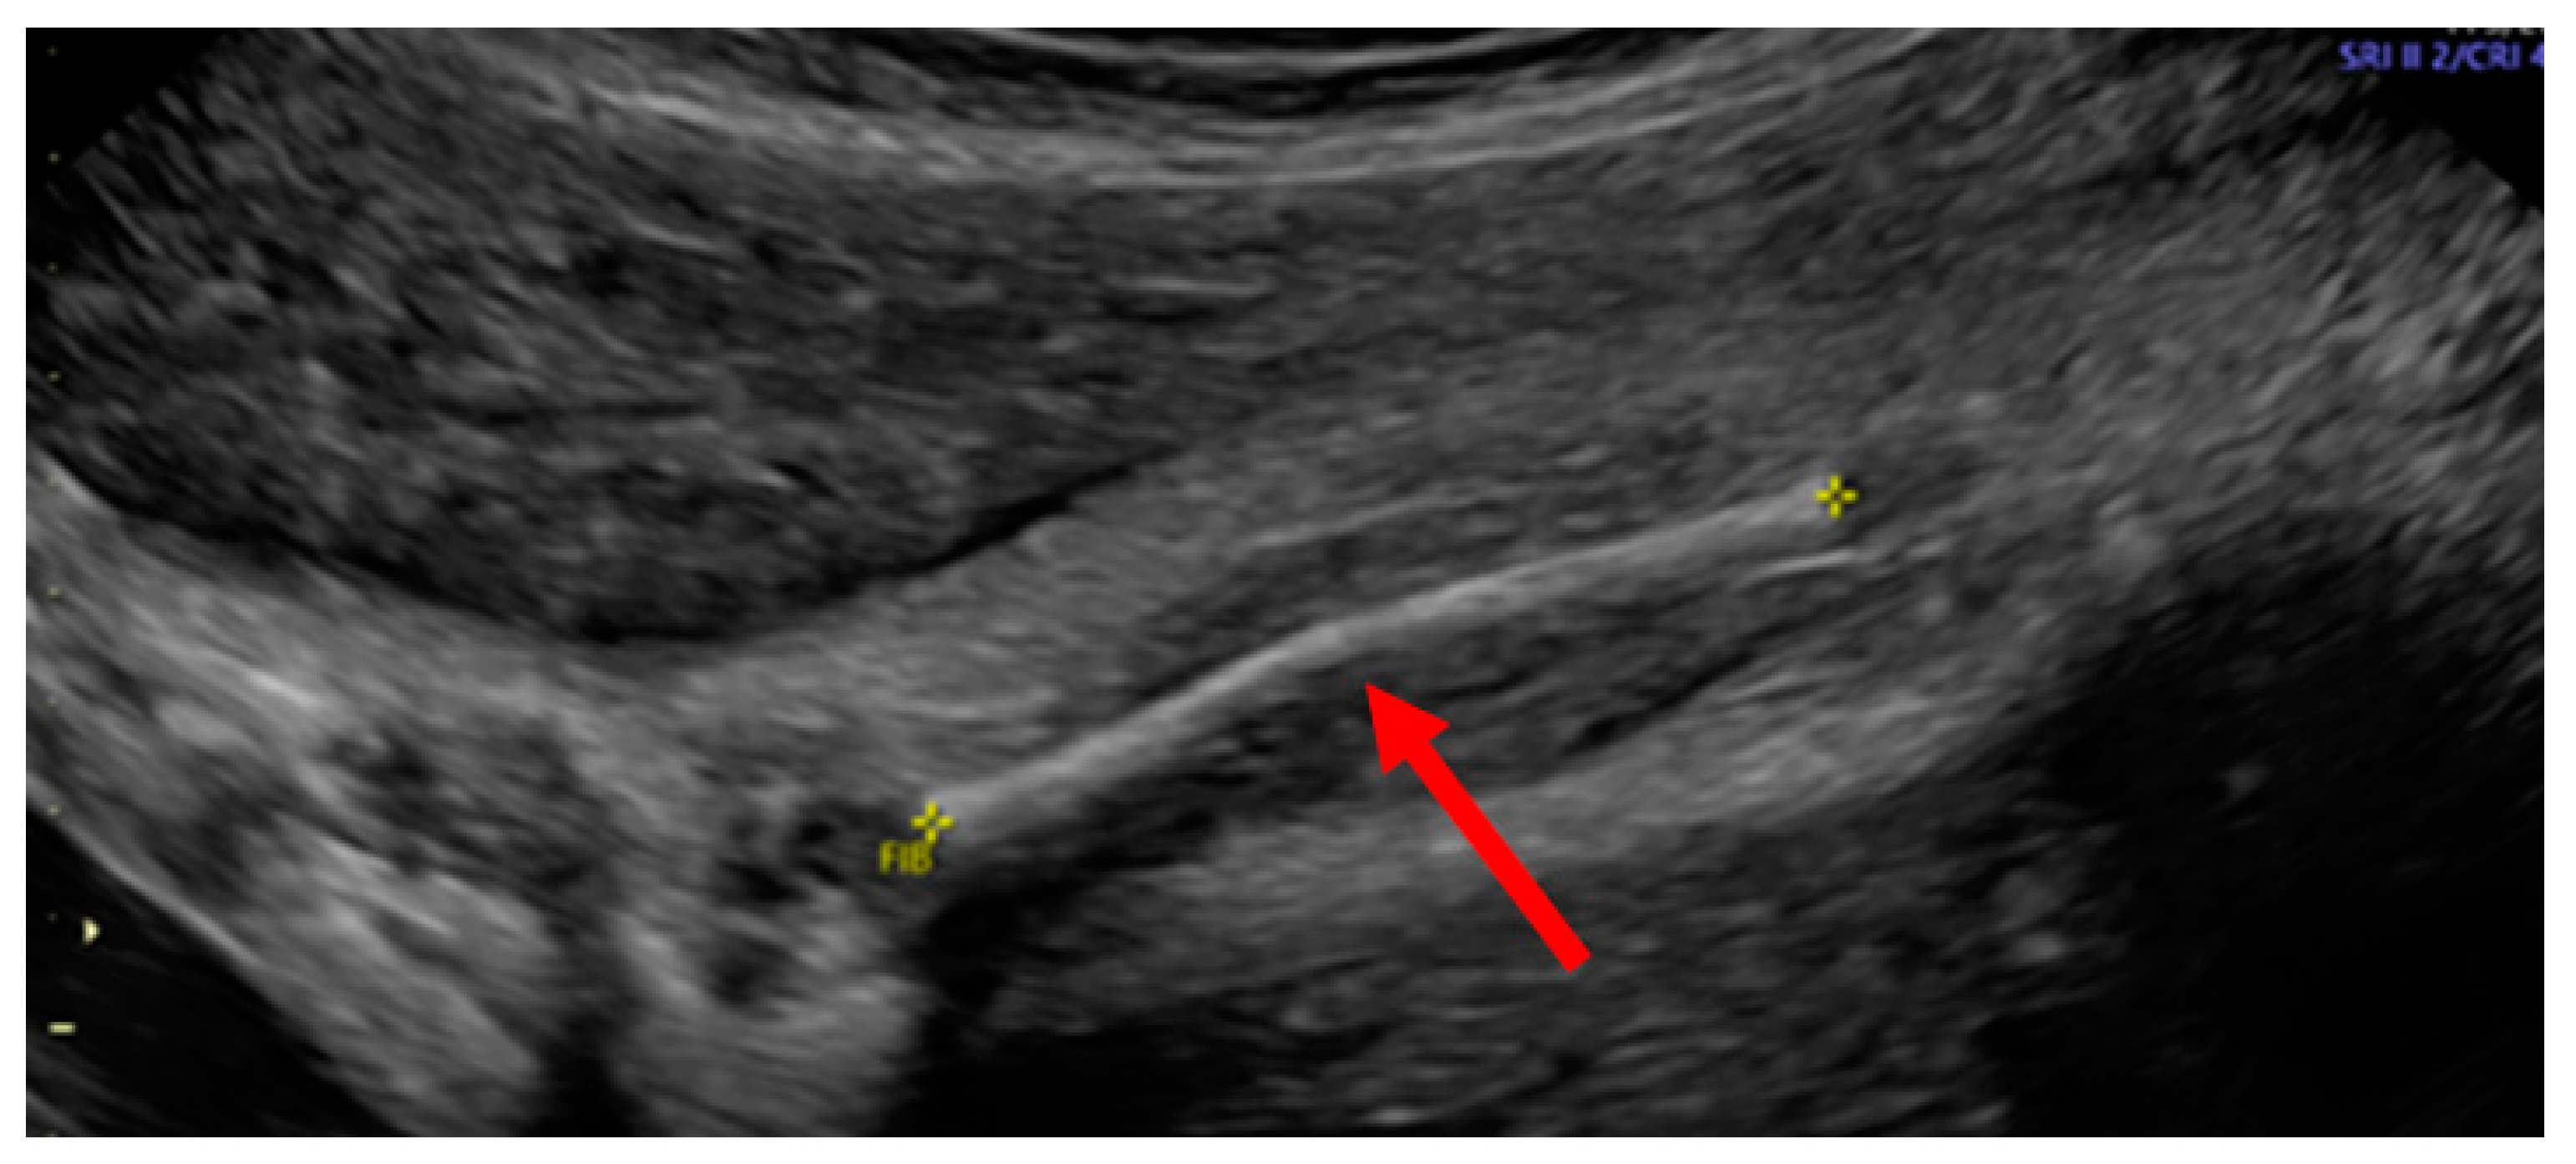

3.1. Phenotypes of the Patient and Parents